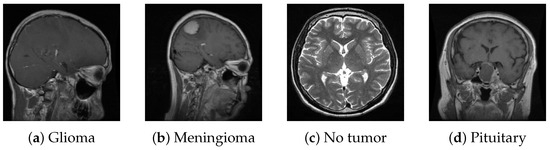

For this study, we utilized a publicly available MRI dataset from Kaggle [40], comprising 7023 brain MRI images sorted into four categories: glioma, meningioma, pituitary, and no tumor. This dataset integrates images from several sources, including Figshare [41], the SARTAJ dataset [42], and Br35H [43], with non-tumor images primarily sourced from Br35H. Figure 10 presents sample images from each class, while Figure 11 illustrates the distribution of these images across each category.

Figure 10.

Samples from the dataset.